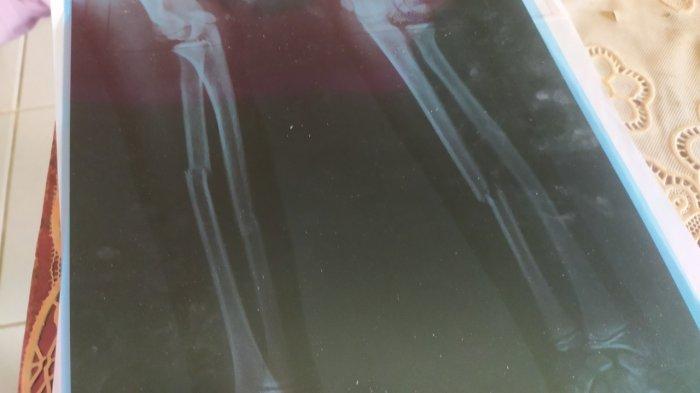

Gara-gara Game Online, Bocah di Sukabumi Pukuli Temannya sampai Patah Tulang, Orang Tua Tak Terima

Anaknya jadi korban kekerasan oleh temannya berinisial R (11) yang tidak terima kalah main game online.